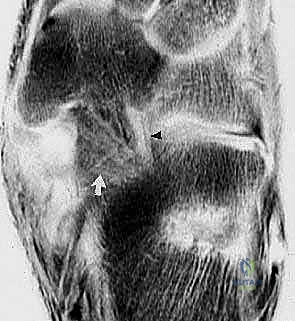

الشكل 1: تشريح مجمع الرباط الزنبركي (منظر ظهري بعد إزالة رأس عظم الكاحل). يوضح هذا المنظر المعقد موقع الأجزاء العلوية الإنسية والسفلية الإنسية. الجزء العلوي الإنسي يقع إنسياً لوتر الظنبوب الخلفي، وينشأ من الجانب العلوي الإنسي للنتوء الداعم لعظم الكاحل والوجه الأمامي لعظم العقب ليلتحم بالعظم الزورقي الإنسي بجوار سطحه المفصلي، مشكلاً دعامة أساسية.

* الأشعة السينية أثناء الوقوف (Weight-bearing X-rays): وهي خطوة أساسية لتقييم زوايا العظام (زاوية ميري Meary's Angle، زاوية التغطية الكاحلية الزورقية Talonavicular Coverage Angle). تكشف هذه الأشعة عن مدى الهبوط والانحراف العظمي.

* التصوير بالرنين المغناطيسي (MRI): يُعد المعيار الذهبي (Gold Standard) لتقييم الأنسجة الرخوة. يوفر الرنين المغناطيسي صوراً عالية الدقة تظهر بوضوح درجة تمزق الرباط الزنبركي، حالة وتر الظنبوب الخلفي، ووجود أي التهابات أو سوائل داخل المفاصل.